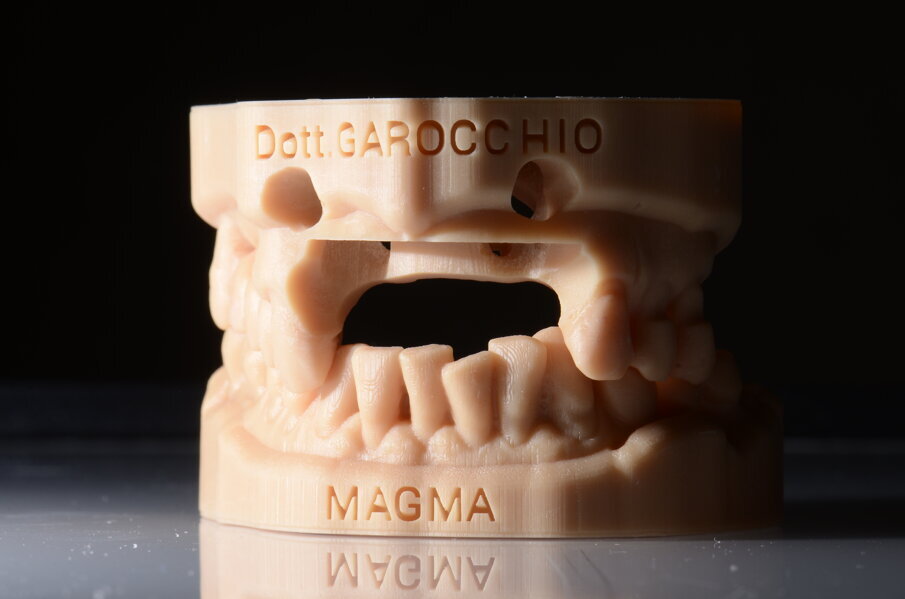

Il piano di trattamento prevede l’estrazione degli elementi dentali, l’inserimento di due impianti e la realizzazione di una protesi fissa di quattro elementi. Il problema da gestire è quello della fase provvisoria. Non è ipotizzabile una protesi mobile e quindi programmiamo di inserire subito dopo l’intervento un provvisorio immediato. Questo ci consente di condizionare da subito i tessuti periimplantari e anche le zone dei ponti. Si rileva un’impronta digitale (Figg. 5, 6), e la programmazione degli impianti viene effettuata con un software di chirurgia guidata (Fig. 7) e la posizione degli impianti nello spazio biologico e nello spazio protesico viene fatta sulla base di una ceratura diagnostica (Figg. 8, 9). Inseriamo gli impianti virtuali nell’osso disponibile (Figg. 10-13) e in relazione all’aspetto protesico correggiamo l’asse di inclinazione degli impianti con componenti secondarie angolate a 17° (Figg. 14, 15). Questo ci consentirà di realizzare una protesi avvitata con i fori situati nella zona palatale.

Fig. 8 - Ceratura diagnostica.

Fig. 9 - Visione occlusale ceratura.

Fig. 19 - Modelli digitali relazionati.

Fig. 20 - Modello master di lavoro.

Fig. 21 - Modello Master e provvisorio pre-chirurgico.